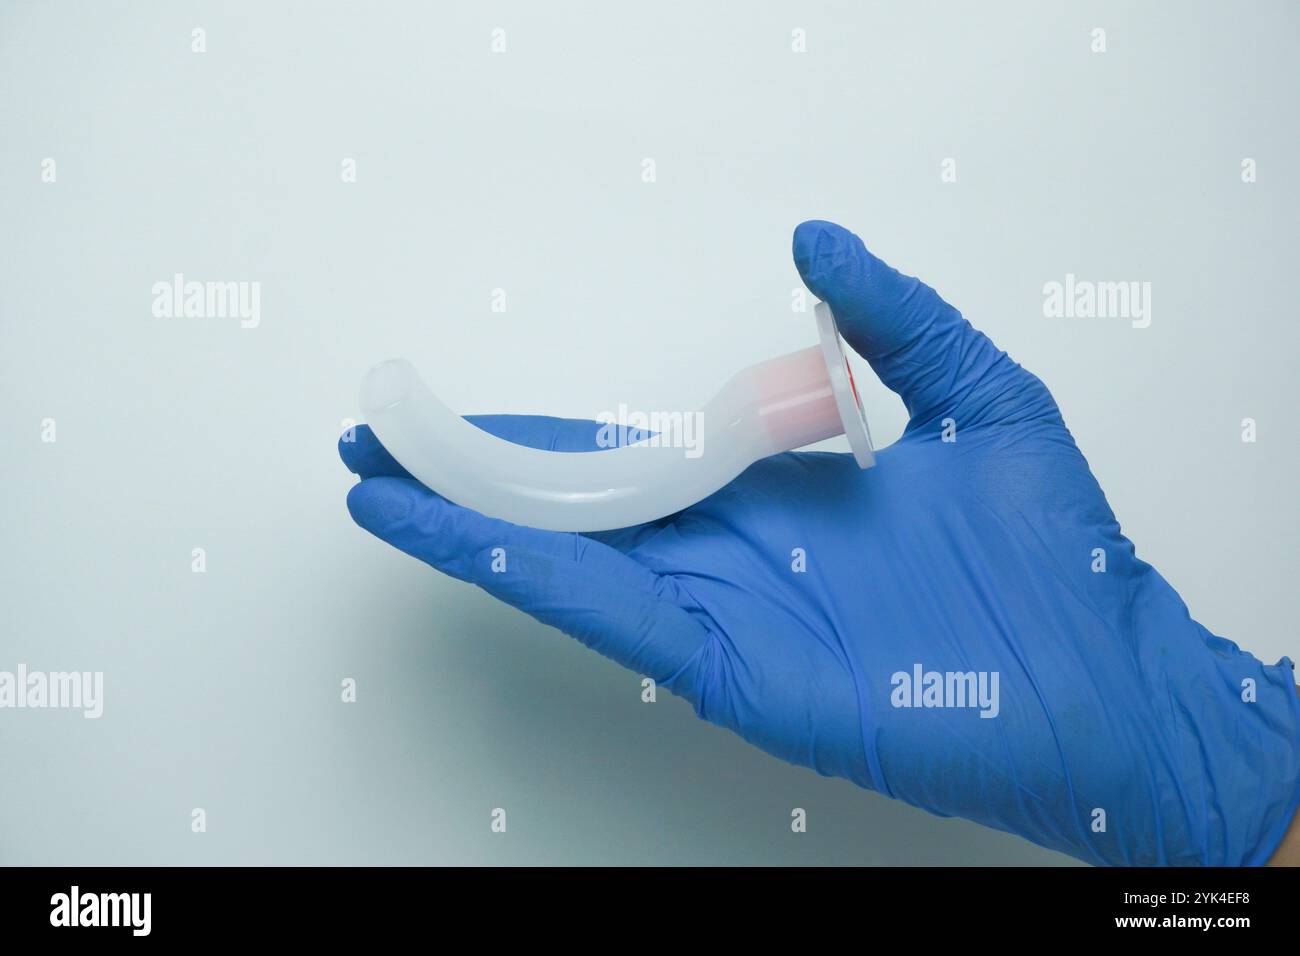

Medical worker wearing medical gloves holding an OPA (Oropharyngeal airway) is a medical device called an airway adjunct that is used in airway manage Stock Photohttps://www.alamy.com/image-license-details/?v=1https://www.alamy.com/medical-worker-wearing-medical-gloves-holding-an-opa-oropharyngeal-airway-is-a-medical-device-called-an-airway-adjunct-that-is-used-in-airway-manage-image631350924.html

Medical worker wearing medical gloves holding an OPA (Oropharyngeal airway) is a medical device called an airway adjunct that is used in airway manage Stock Photohttps://www.alamy.com/image-license-details/?v=1https://www.alamy.com/medical-worker-wearing-medical-gloves-holding-an-opa-oropharyngeal-airway-is-a-medical-device-called-an-airway-adjunct-that-is-used-in-airway-manage-image631350924.htmlRF2YK4EF8–Medical worker wearing medical gloves holding an OPA (Oropharyngeal airway) is a medical device called an airway adjunct that is used in airway manage